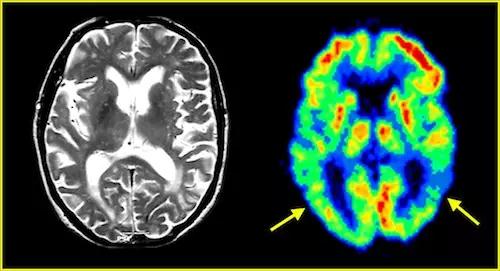

脑萎缩的大脑检查图

老年脑萎缩是以病理改变命名的一种脑病,是指各种原因所引起的脑组织结构体积缩小,脑实质减少,脑重量减轻,细胞数目减少,脑回变平,脑沟增宽增深,脑 室、脑池和蛛网膜下腔扩大。并有轻度胶质增生及脑动脉不同程度退行性病变,是一种慢性进行性疾病,主要表现为记忆力减退,情绪不稳,思维能力减退,注意力 不能集中,严重时发展为痴呆,终至智力丧失为其临床特征。